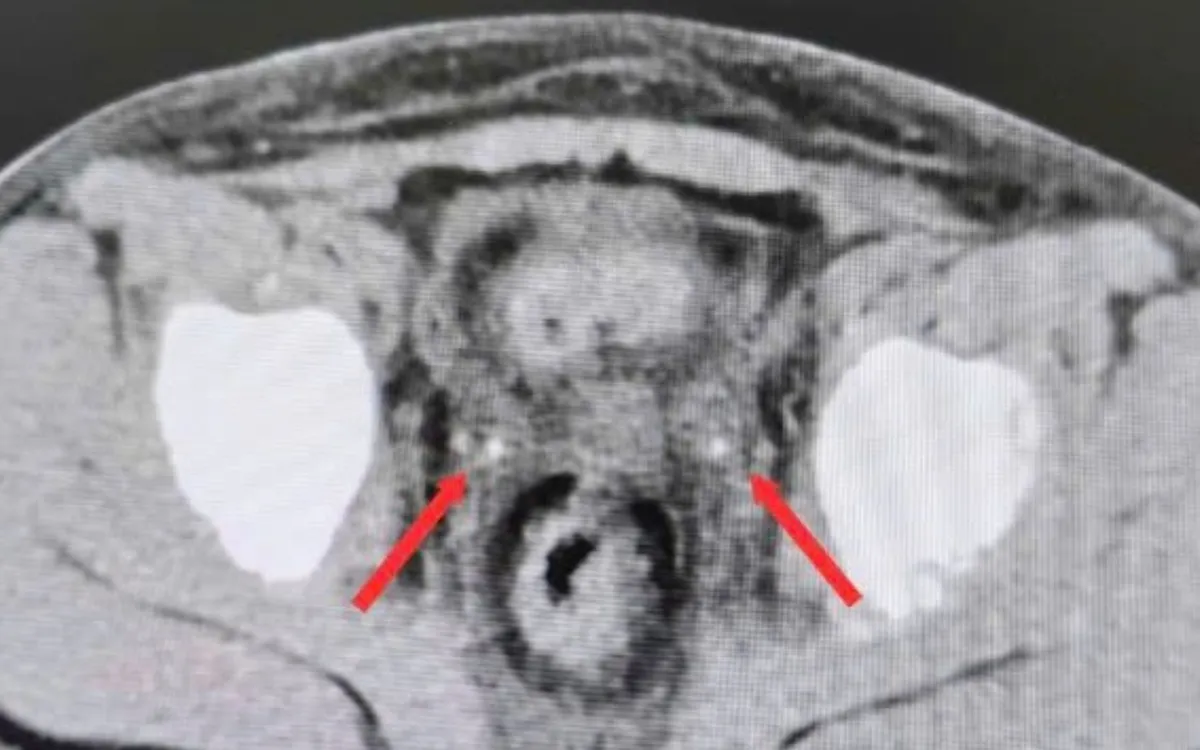

Chuyển đến Bệnh viện Nhi đồng 2 trong tình trạng không có nước tiểu, siêu âm không thấy nước tiểu trong bàng quang. Kết quả CT bụng không cản quang ghi nhận thận ứ nước hai bên, niệu quản giãn và sỏi kẹt đoạn cuối hai bên (phải 3x7mm, trái 3x20mm). Bệnh nhi được mổ cấp cứu trong đêm, nội soi bàng quang đặt ống thông JJ ngược dòng hai bên.